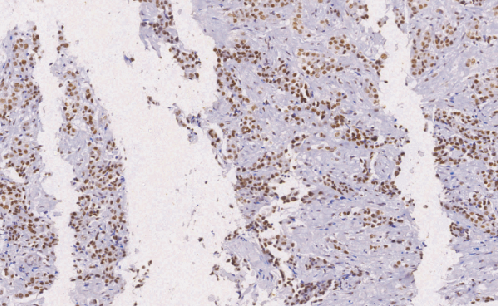

INI-1鼠抗人INI-1单克隆抗体

INI-1基因编码一个功能未知的HSWI/SNF染色质重塑复合物蛋白在恶性横纹肌样瘤(MRT)中容易发生突变或缺失。MRT较髓母细胞瘤和原始神经外胚层肿瘤的总体生存期要低很多,因此,区分MRT与髓母细胞瘤和原始神经外胚层肿瘤是很有必要的。INI-1通常在MRT中缺失表达,而绝大多数髓母细胞瘤和原始神经外胚层肿瘤都有表达INI-1。软组织中的上皮样肉瘤在组织学上经常显示横纹肌样特征,而且都不表达INI-1。有时很难将两者区分,然而上皮样肉瘤CD34和B-catenin阳性,MRT两者均阴性

- 阳性部位:胞核

- 适用组织:石蜡切片

- 预处理:热修复